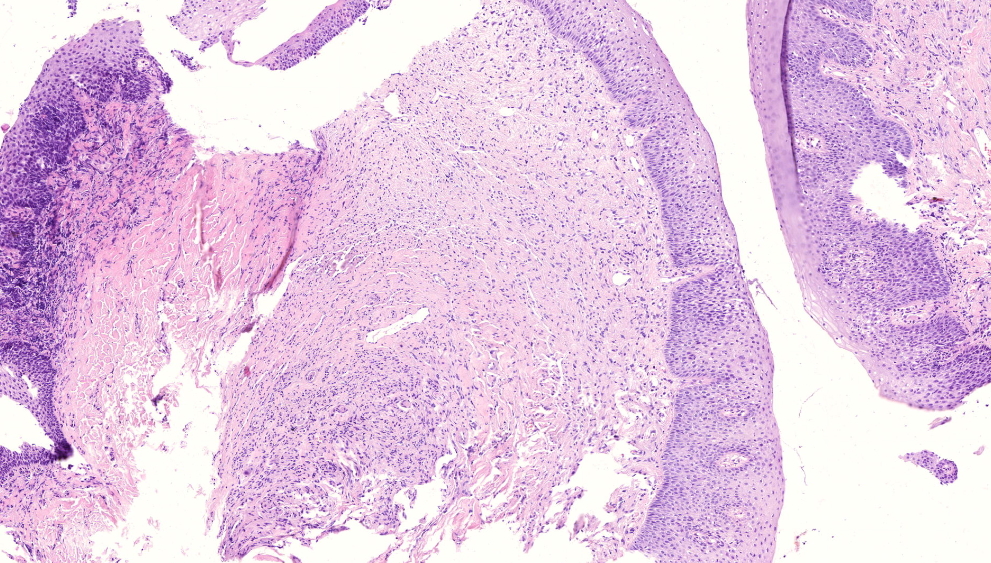

From www.pathologyoutlines.com

Pathology Outlines Subgemmal neurogenous plaque Plaques On Tongue You might also experience bad breath, a hairy tongue and irritation. Leukoplakia is a condition that creates white patches on your tongue, gums or the inside of your cheeks. Mouth irritants and irritating activities,. Your whole tongue might be white, or you could just have white spots or patches on your tongue. White tongue refers to a white covering or. Plaques On Tongue.